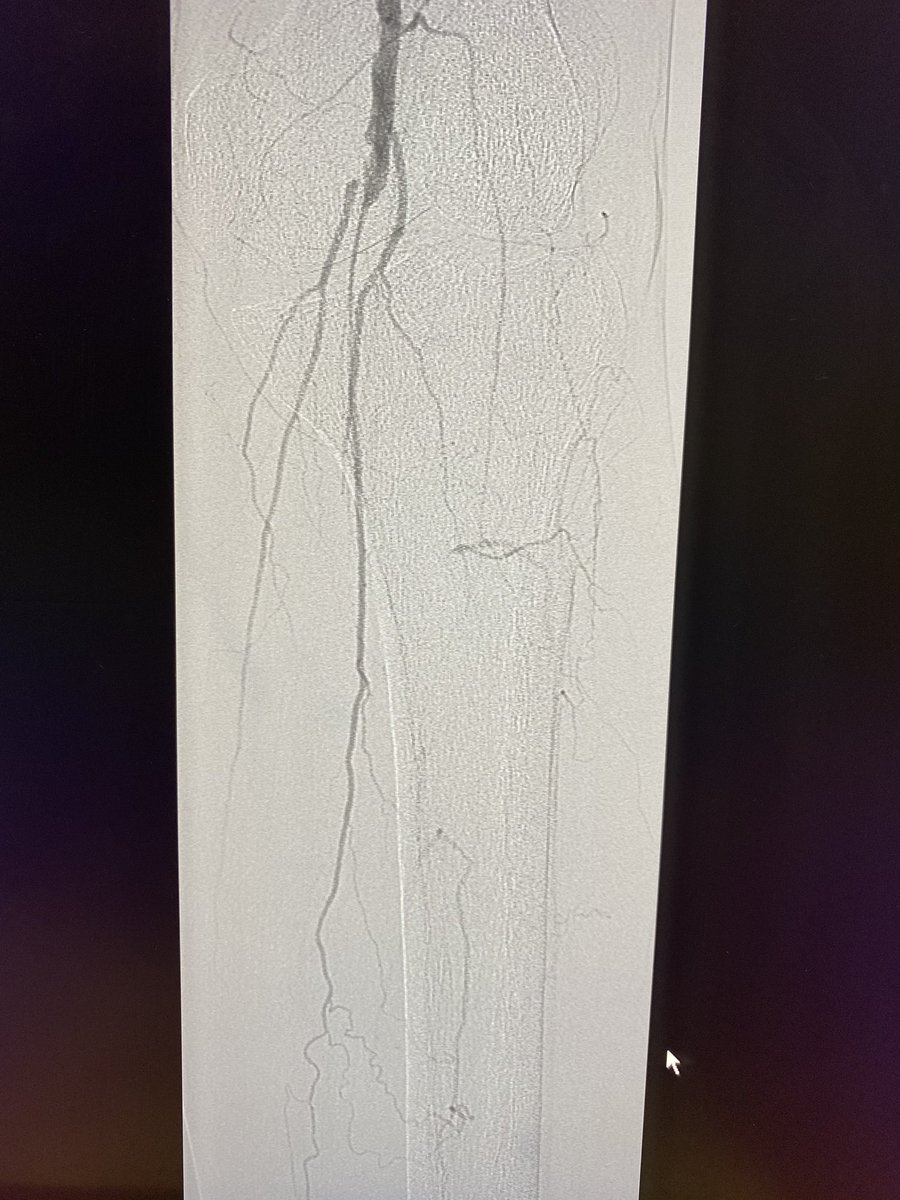

Transradial Infrapopliteal Atherectomy, Angioplasty and Stenting for Cri... youtu.be/Gf8tdMXcBls via @YouTube